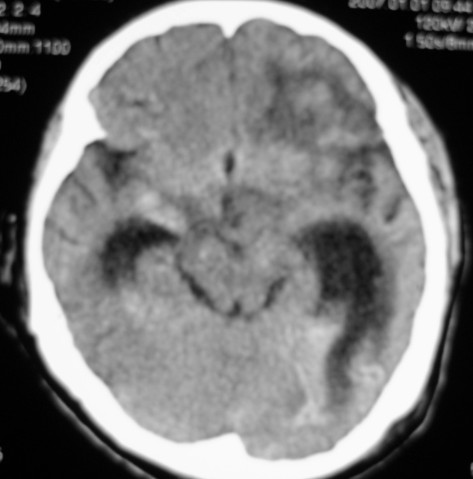

标题: CT9218:男性,50岁,脑出血术后复查,两次片相隔半月,请分 [打印本页]

标题: CT9218:男性,50岁,脑出血术后复查,两次片相隔半月,请分

第一次ct片脑出血术后,出血吸收期。第二次ct 片左颞顶枕部及右颞顶部有脑回样高密度影。考虑珠网膜下腔出血。脑出血术后改变,脑出血恢复期 并脑积水。

第一次ct片脑出血术后,出血吸收期。第二次ct 片左颞顶枕部及右颞顶部有脑回样高密度影。考虑珠网膜下腔出血。脑出血术后改变,脑出血恢复期 并脑积水